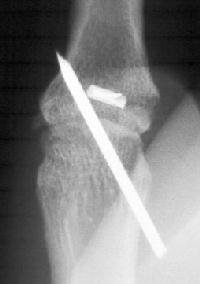

and a film showing the bone anchor and a temporary transarticular pin.